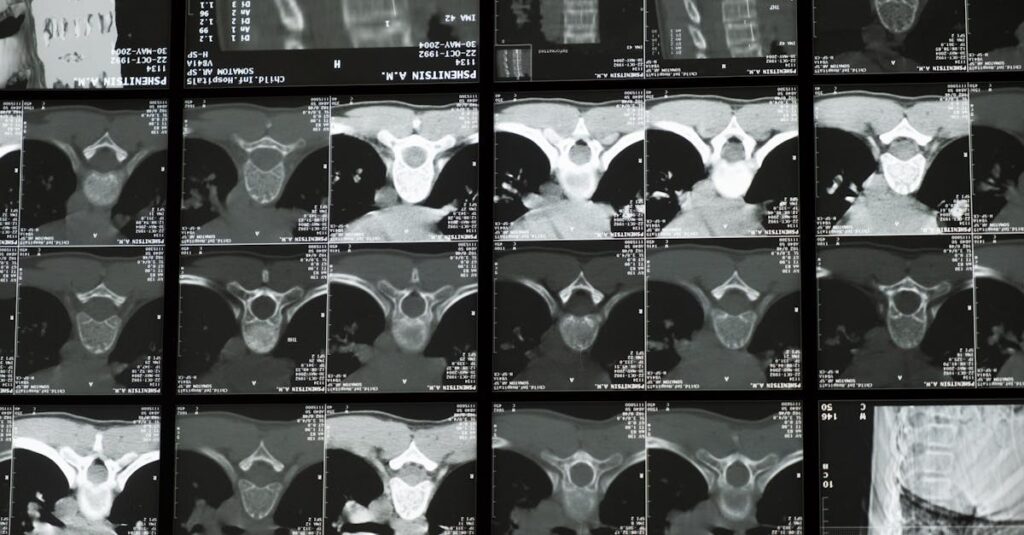

Quels examens permettent de diagnostiquer un bombement discal?

Une IRM ou une radiographie sont les outils les plus couramment utilisés pour diagnostiquer un bombement discal.